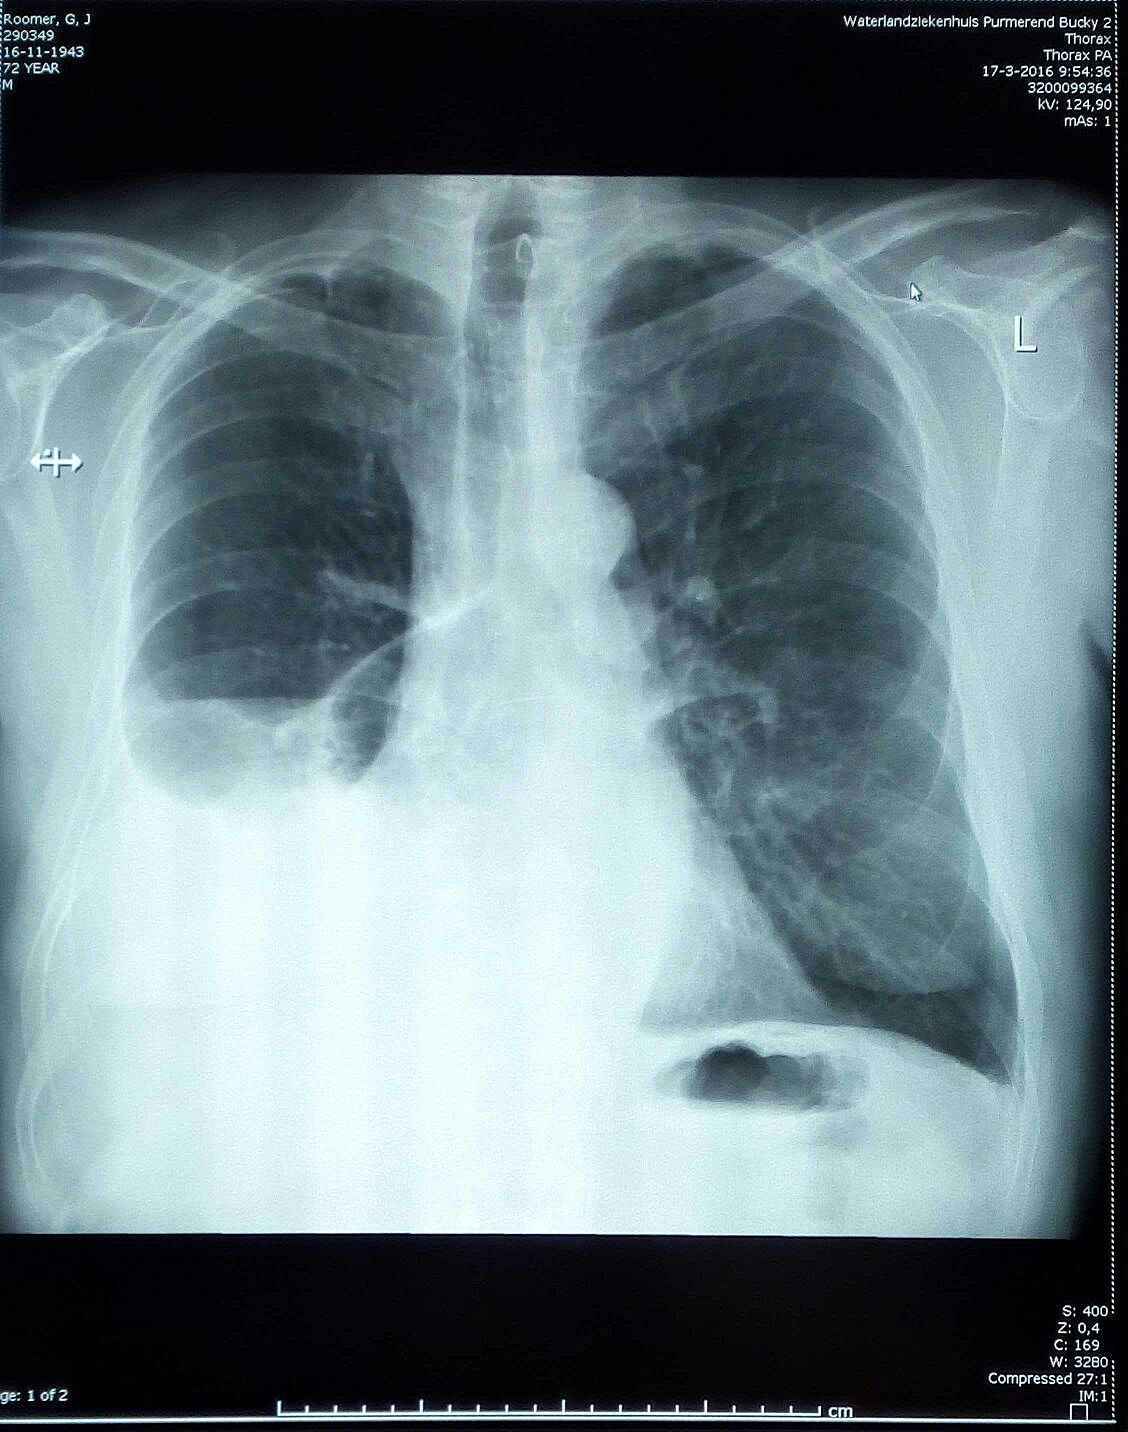

Half maart 2016